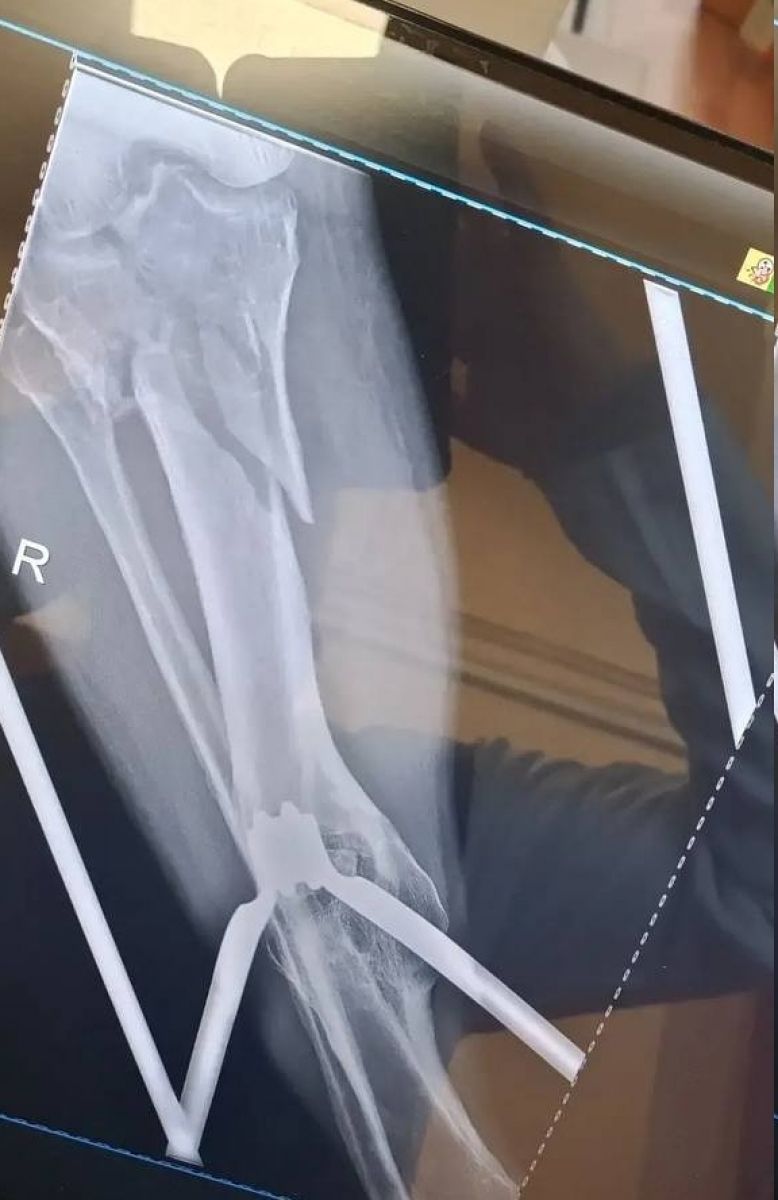

Врачи городской больницы № 4 «Липецк-Мед» провели сложнейшую 3-часовую операцию, чтобы спасти мужчину, который попал в страшное ДТП 25 февраля. При поступлении медики диагностировали у него внутрисуставные переломы верхних отделов обеих голеней – они были раздроблены.

Оперировала мужчину бригада во главе с завотделением травматологии Дмитрием Соколовым и травматологом Евгением Крюченковым. Хирурги приняли решение оперировать сразу обе ноги. Почти три часа врачи по кусочкам собирали разрушенные кости голеней.

Сейчас самое опасное позади, пациента уже перевели из реанимации в профильное отделение. Его состояние стабилизировалось. Теперь ему предстоят повторные операции, чтобы убрать скрепляющие конструкции после сращения костей, а затем долгий процесс восстановления и реабилитации.